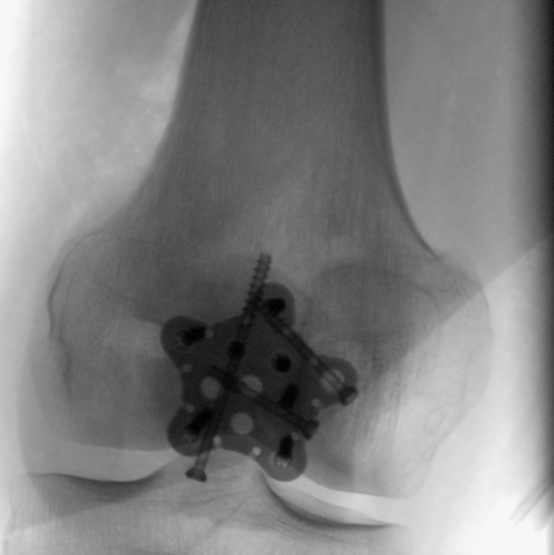

Hier der Vorher-Nachher-Vergleich.

Ich glaube, die haben mir einen

Shimano-Cleat ins Knie eingebaut

Das Titan wollen die allerdings wohl irgendwann wiederhaben. Nach 4, 5 Monaten, wenn alles richtig verheilt ist, muss ich nochmal unters Messer, da das wohl sonst auf Dauer stören kann.